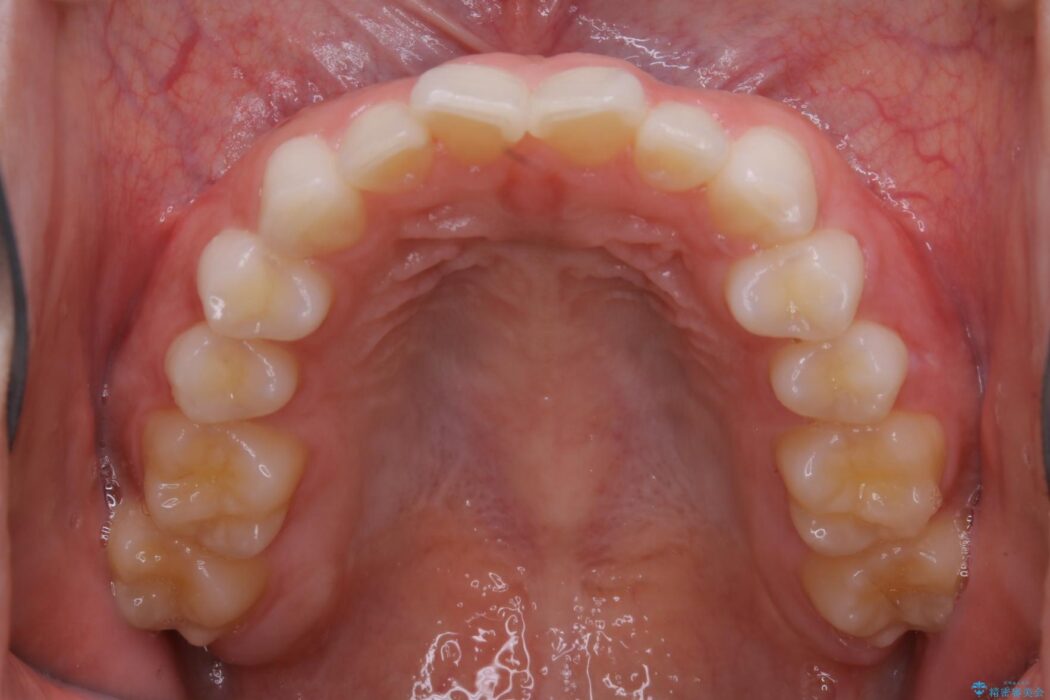

半年という短期間でスピード治療が完了しました。

治療期間、治療後の出来ともに大変ご満足いただけました。

患者様の歯の状態によってはマウスピース治療でも部分矯正のように短い治療期間で歯列の矯正をすることが可能です。